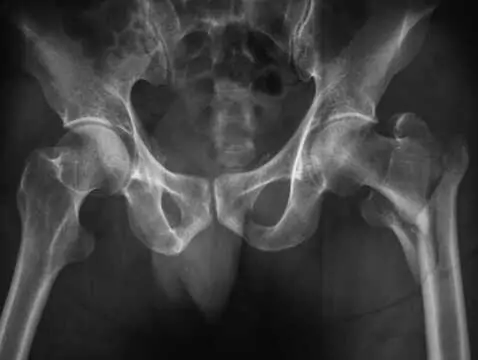

Od sierpnia nieustannie czuje ogromne pieczenie w kości ogonowej i dole lewego pośladka/dole pleców. Jest to piekący ból, który praktycznie nigdy nie przechodzi. Czuję go głęboko w ciele, więc zapewne to jakiś nerw. Próbowałem wszystkiego, ale z dnia na dzień jest coraz gorzej, a minęło już kilka dobrych miesięcy. Piecze tak samo mocno zarówno podczas stania, jak i siedzenia. Czytałem o mięśniu gruszkowym i myślę, że może mieć on coś z tym wspólnego. Jednak mieszkam w małej wsi i najbliższymi miejscowościami są tylko Nowy Sącz, Gorlice i Krynica-Zdrój.